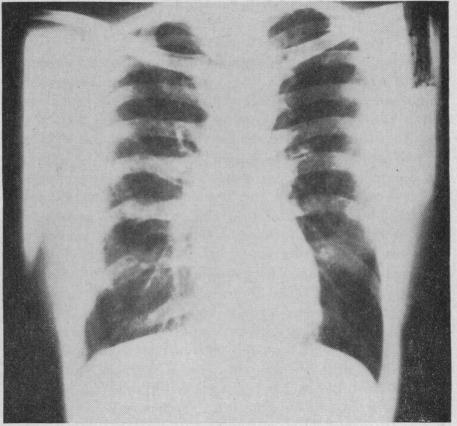

Eosinophilic pneumonia (Loeffler's syndrome); report of a case treated with ACTH.

Calif Med. 1951 Nov;75(5):365-7.